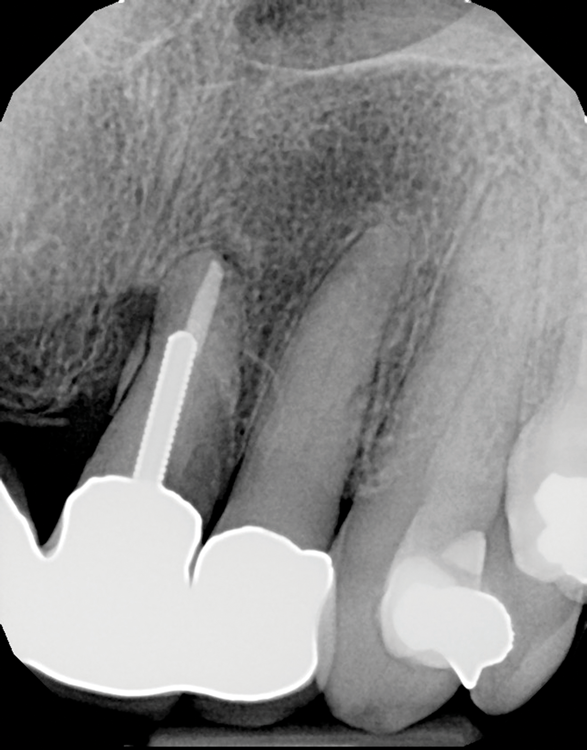

Question 11: Which materials cannot be seen in the print of the X ray?

Question 12: What option cannot be selected for the following X ray?

Question 13: What option cannot be selected for the following X ray?

Question 14: Which surface shows overhang restoration?

Question 15: Which surface shows overhang in the restoration?

Question 16: Which surface shows overhang?

Question 17: Which surface shows overhang?

Question 18: Which surface shows overhang?

Question 19: Which option can be chosen for the tooth # 3.6?

Question 20: which tooth shows defective resotration?